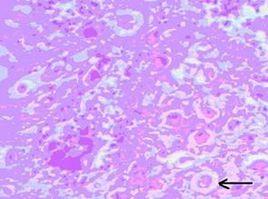

白喉桿菌傳染。白喉桿菌在易感者的上呼吸道(通常為咽部)黏膜表層組織內或體表皮膚內繁殖 分泌外毒素 外毒素滲入局部及周圍組織 引起組織壞死和急性假膜性炎症 從血管滲出的液體中含有易凝固的纖維蛋白 將炎性細胞 黏膜壞死組織和白喉桿菌凝固在一起而形成假膜 假膜呈灰白色 邊緣較整齊 假膜與黏膜下組織緊密粘連 不易拭去 #少數病人的病變可侵入深層組織而形成潰瘍面 喉 氣管及支氣管黏膜上皮具有纖毛 形成的假膜和黏膜粘連不緊 易從氣管切口處噴出。